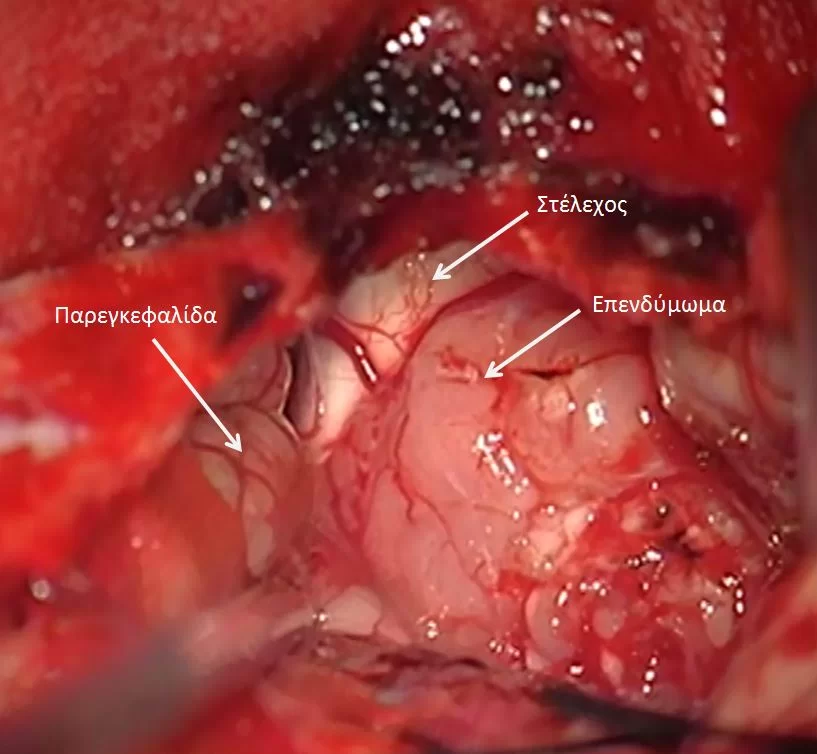

Η μέγιστη ασφαλής αφαίρεση συνιστάται σε όλους τους ασθενείς με ενδοκρανιακό επενδύμωμα. Η ολική εκτομή είναι ο στόχος αλλά δεν είναι πάντοτε εφικτή λόγω της εμπλοκής του στελέχους ή της εγγύτητας με άλλες κρίσιμες δομές.